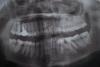

Здравствуйте! при каждом походе к стоматологу все говорят что нужно обратиться к ортодонту! а мне очень страшно что скажут удалять кучу зубов! пожалуйста, подскажите какой может быть назначен план лечения для моих зубиков в области ортодонтии! за ранее, большое спасибо!